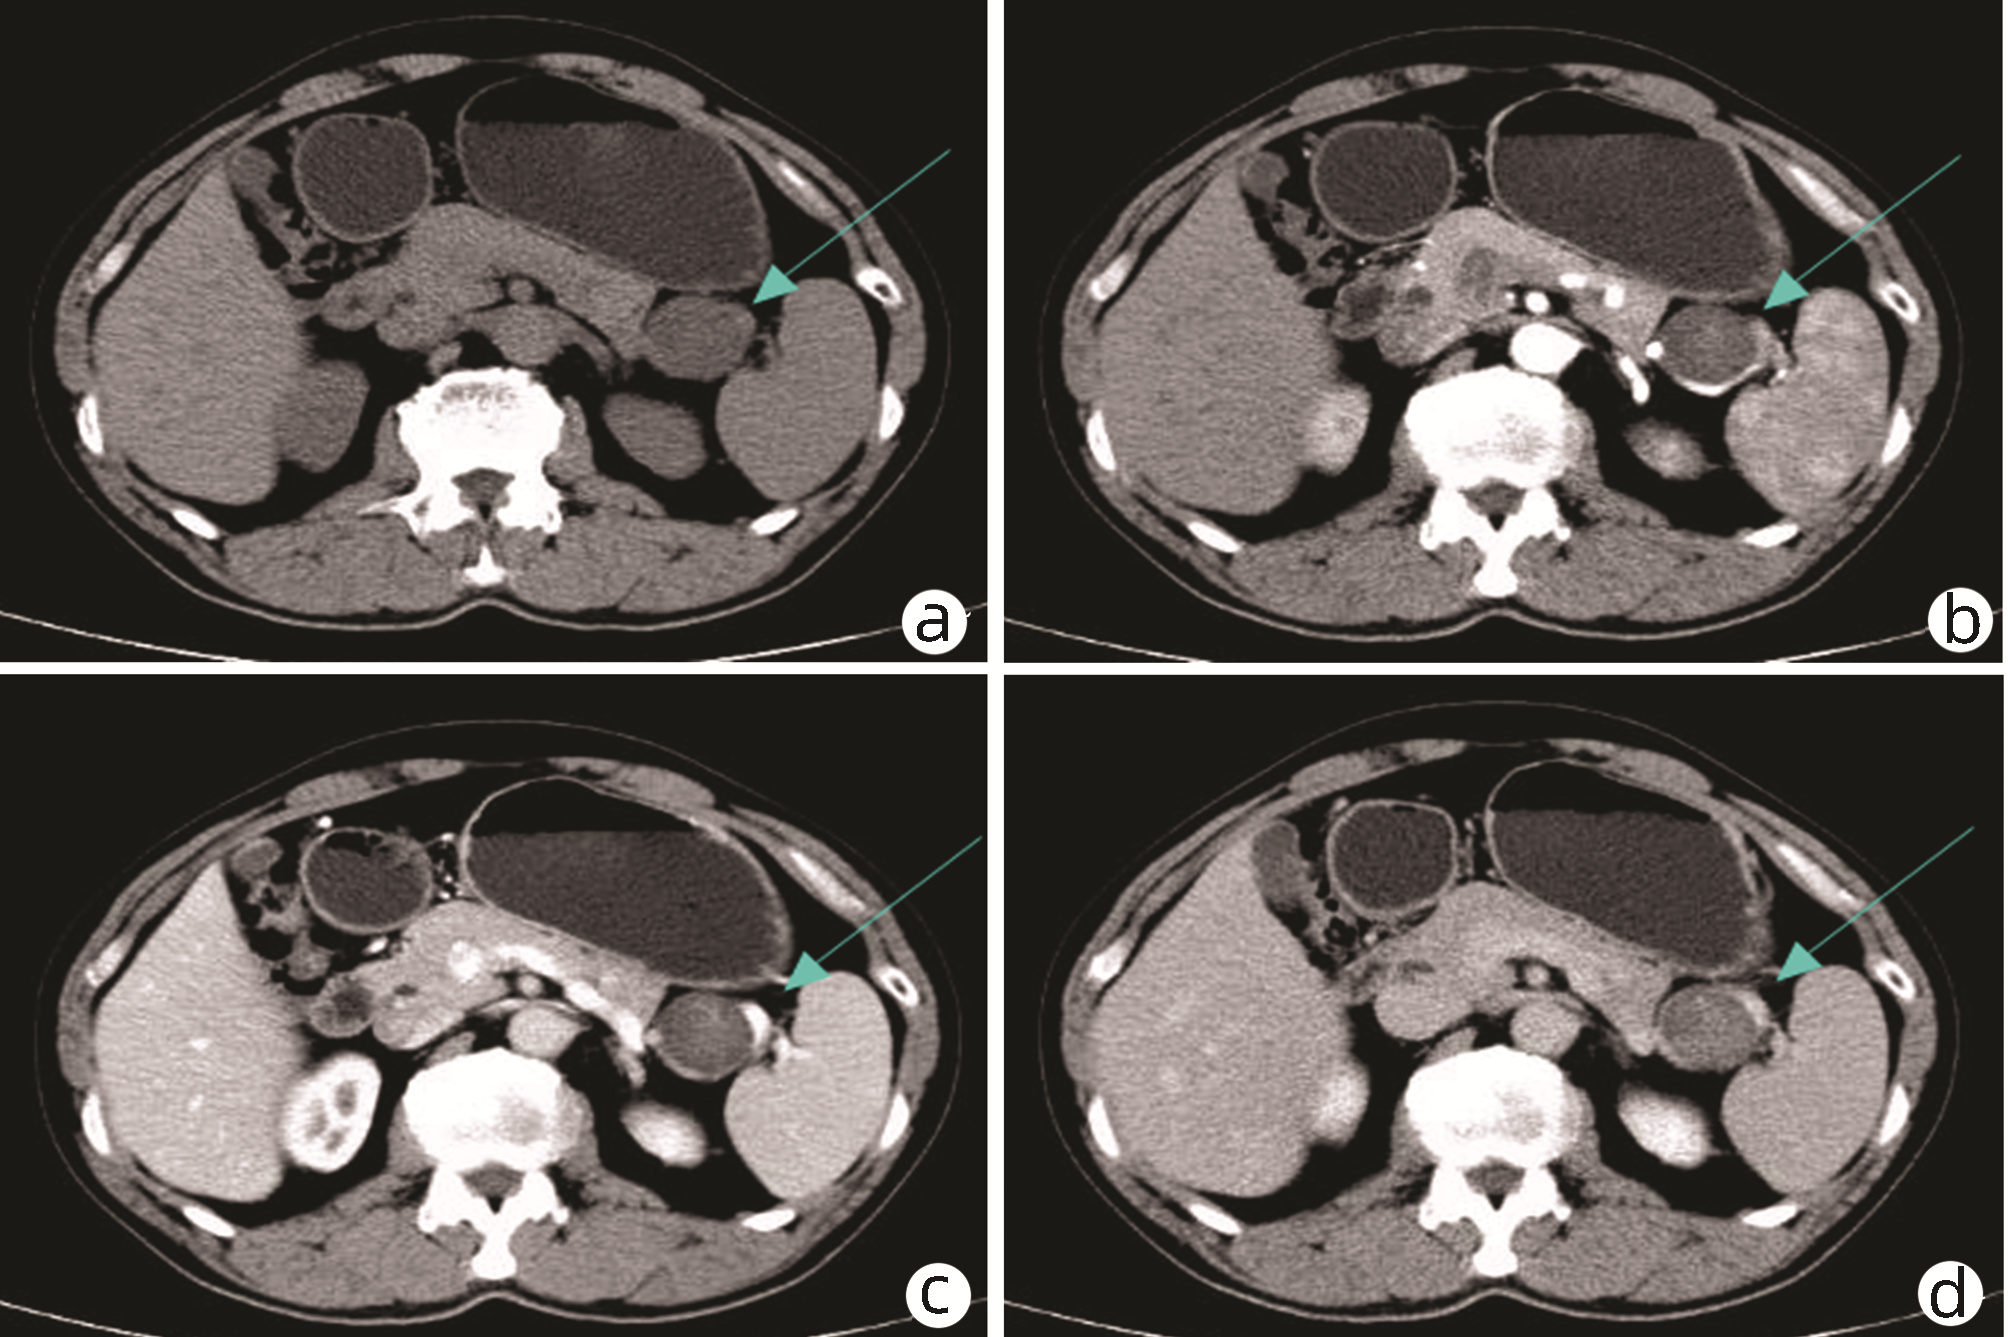

仑伐替尼联合信迪利单抗二线治疗肝内胆管癌的效果和安全性

丁晓燕, 孙巍, 申燕军, 滕颖, 许雅文, 李文东, 陈京龙

2022, 38(8): 1813-1818. DOI: 10.3969/j.issn.1001-5256.2022.08.018

摘要(2283) HTML (1725) PDF (2697KB)(159)

摘要:

目的  初步探索仑伐替尼联合信迪利单抗在肝内胆管癌二线治疗中的疗效和安全性。  方法  回顾性分析北京地坛医院医院2019年10月31日—2021年10月31日收治的无法手术根治的肝内胆管癌二线治疗患者的临床资料,患者使用仑伐替尼联合信迪利单抗治疗。随访患者,采用RECIST1.1标准评价疗效。主要观察终点为至疾病进展时间(TTP),次要观察终点为肿瘤客观缓解率(ORR)、疾病控制率(DCR)、总生存期(OS)和安全性。Kaplan-Meier法绘制生存曲线,组间差异采用log-rank检验。  结果  共27例患者入组,其中男15例(55.6%),女12例(44.4%),中位年龄58岁(33~73岁)。患者中位TTP为5.5个月(95%CI:1.7~9.3),13例(48.1%)患者因疾病死亡,中位OS为11.2个月(95%CI:5.0~17.4)。总体ORR为40.7%,DCR为70.3%。66.7%发生了不同程度的不良事件。ALT和AST升高分别为44.4%,高血压37.0%,胆红素升高为29.6%,腹泻29.6%;尿蛋白、食欲下降和乏力分别为25.9%。无治疗相关的死亡;仅有1例发生Ⅳ度免疫相关性肝脏毒性,经激素治疗后缓解,无后遗症,导致信迪利单抗永久性停药。合并淋巴结转移的患者中位TTP与无淋巴结转移患者比较显著缩短(4.5个月 vs 18.8个月,P=0.035), 获得疾病缓解的患者,中位TTP显著延长[11.6个月(95%CI:5.6~17.6) vs 2.8个月(95%CI:1.8~3.8),P<0.001];合并淋巴结转移的患者中位OS有缩短趋势[9.6个月(7.9~11.3)vs 21.9个月(95%CI:0~44.9),P=0.053], 疾病获得缓解的患者中位OS显著延长[16.6个月(95%CI:9.0~24.2) vs 6.9个月(95%CI:3.6~10.2),P=0.011]。  结论  仑伐替尼联合信迪利单抗二线治疗肝内胆管癌临床效果显著,严重不良事件发生率低,是一种安全、有效的治疗方案。